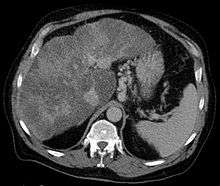

Gastric varices are dilated submucosal veins in the stomach, which can be a life-threatening cause of bleeding in the upper gastrointestinal tract. They are most commonly found in patients with portal hypertension, or elevated pressure in the portal vein system, which may be a complication of cirrhosis. Gastric varices may also be found in patients with thrombosis of the splenic vein, into which the short gastric veins which drain the fundus of the stomach flow. The latter may be a complication of acute pancreatitis, pancreatic cancer, or other abdominal tumours, as well as hepatitis C. Gastric varices and associated bleeding are a potential complication of schistosomiasis resulting from portal hypertension.

The Sarin classification of gastric varices identifies four different anatomical types of gastric varices, which differ in terms of treatment modalities.